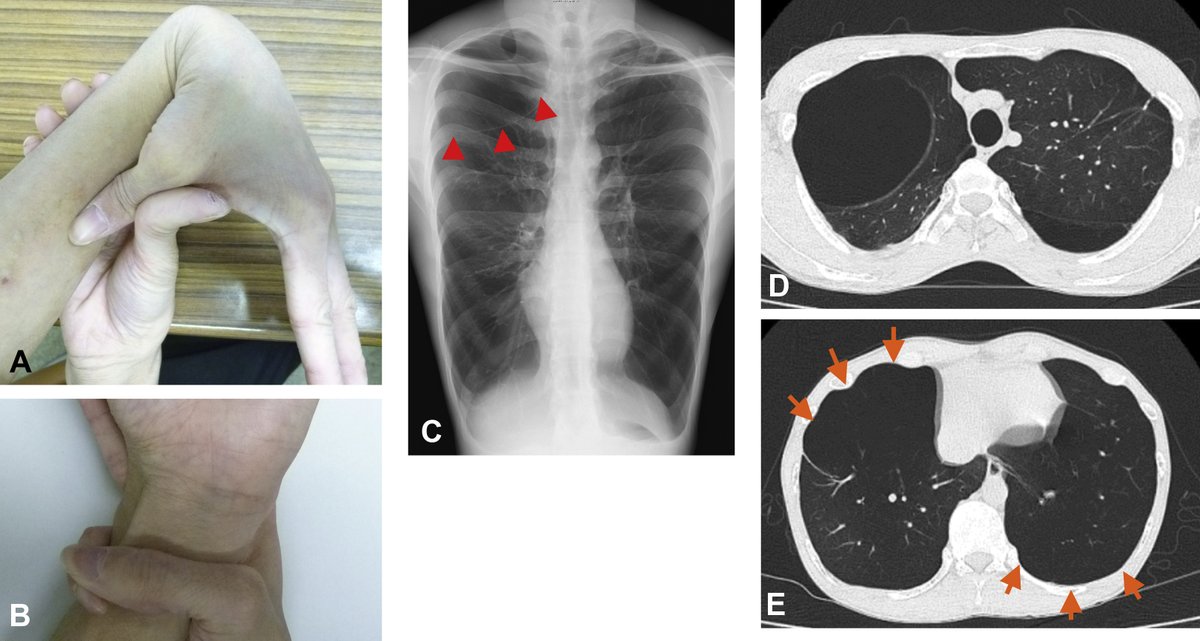

35-year-old Patient presents with hematuria and flank pain and a past history of tuberculosis. NCCT scan of the abdomen is done and given below. What is the urinary bladder in this condition? A. Corkscrew bladder B. Christmas tree bladder C. Thimble bladder D. Putty bladder